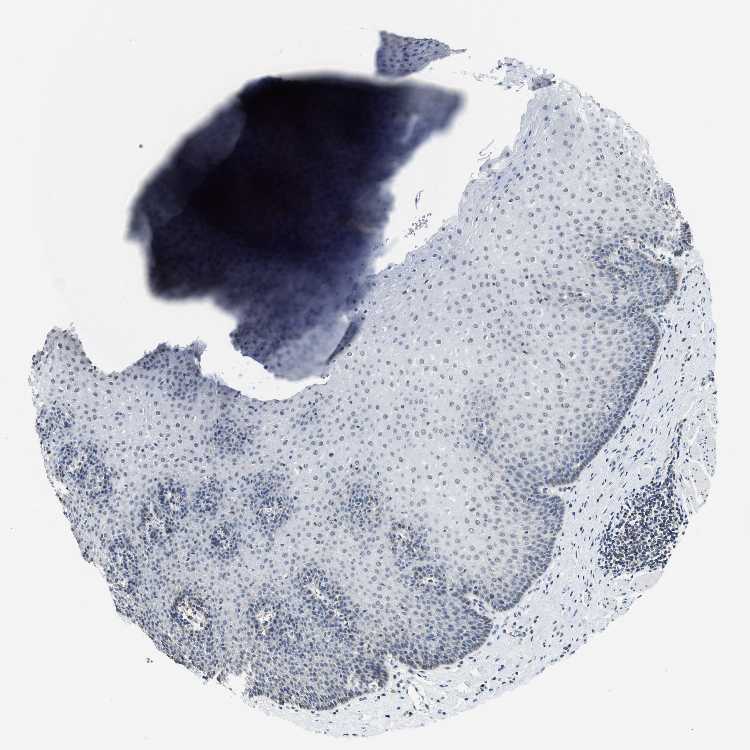

ESOPHAGUS - Antibody stainingi

Antibody staining in the annotated cell types in the current human tissue is reported as not detected, low, medium, or high, based on conventional immunohistochemistry profiling in selected tissues. This score is based on the combination of the staining intensity and fraction of stained cells.

Each image is clickable and will lead to virtual microscopy that enables deeper exploration of all samples and also displays staining intensity scores, fraction scores and subcellular localization as well as patient and tissue information for each sample.

Antibody HPA001598Antibody HPA018905

Squamous epithelial cells LowLow